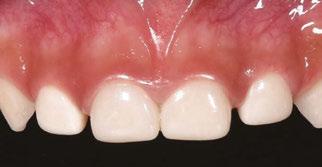

Several clinical solutions exist for primary anterior teeth with multisurface decay. Full coronal restoration of carious primary incisors may be indicated when caries is present on multiple surfaces, pulpal therapy is indicated, caries may be minor, but oral hygiene is very poor, or in a child with severe early childhood caries or a high caries risk diagnosis.1 Depending on the clinical scenario, a minimally invasive approach with the utilization of a high viscosity glass ionomer cement (HVGIC), with or without the combination of silver diamine fluoride (SDF) in a strip crown form, may pause the caries progression and provide an adequate clinical solution. Resin composite strip crowns have shown 80% retention rates and adequate parental satisfaction,1-4 although composite resin strip crowns have shown lower retention rates in teeth with decay involving three or more surfaces and particularly in children with a high caries risk4-6 (Figure 1). This could be from the continued high caries risk behaviors of the patient, as composite resin strip crowns in this population have shown to have increased inflamed marginal gingiva and gingival bleeding, increased plaque retention along the restoration, and loss of some restorative material.5,6

2: NuSmile® Anterior Zirconia crowns at 2-year follow up. Note the high amount of plaque accumulations along the untreated cuspid and existing stainless-steel crowns

This review discusses three clinical cases in which NuSmile® ZR (NuSmile, Houston, Texas) anterior pediatric zirconia crowns were the correct clinical decision in varying clinical scenarios.

Figure 1: Occlusal films at recall visit in high caries risk patients showing loss of material and recurrent decay in composite resin strip crowns Figure